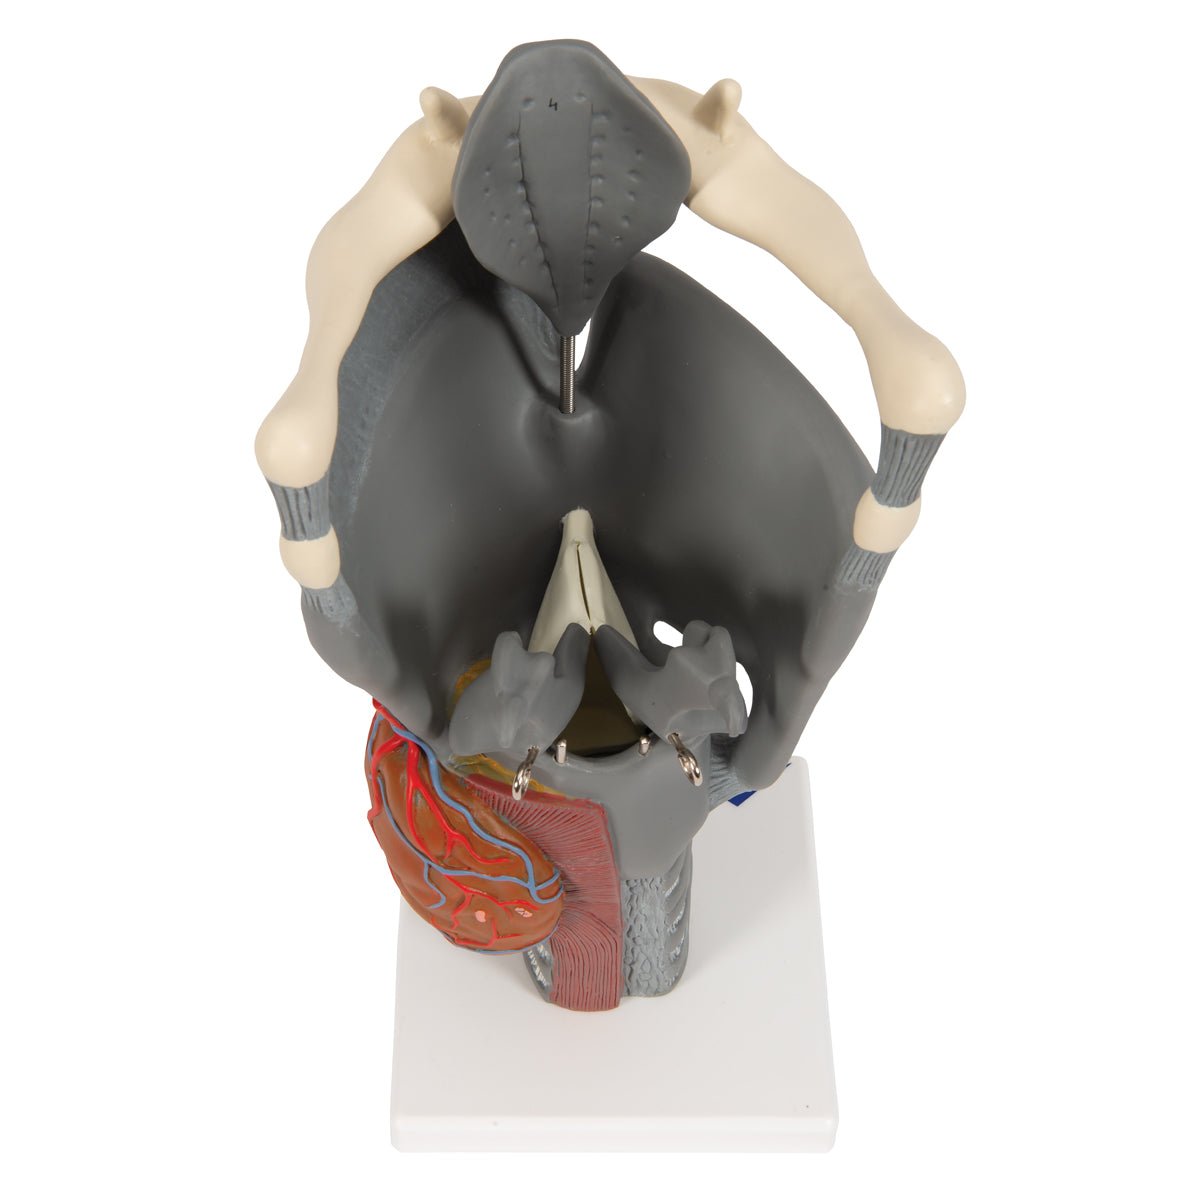

Salg af anatomiske modeller er det bærende element i eAnatomi, selvom vi også bruger mange ressourcer på at udvikle vores egne anatomiske materialer som fx plakater. Anatomiske modeller anvendes til forskellige formål og kan både vise afgrænset væv, organer samt organsystemer. Søger du en simpel model af knoglevæv eller måske en avanceret torso-model baseret på MRI teknologi, kan du finde det hele på eanatomi.com.